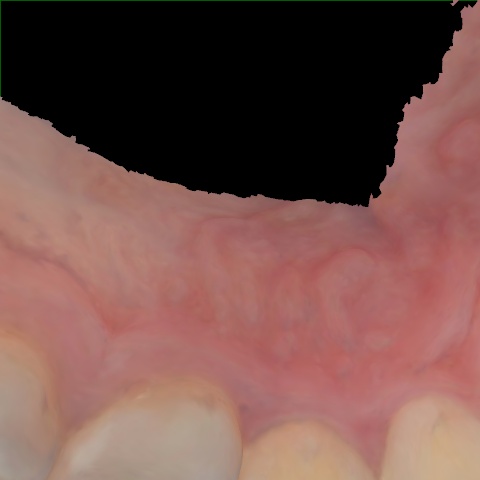

Image 1320 / 1535

NHD39990

Annotated as "Good"

Original Image Rendering Image